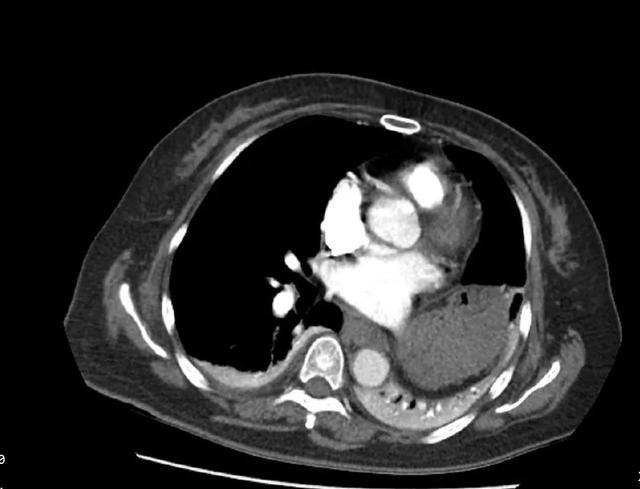

CT检查提示右肺下动脉栓塞,延伸到右肺动脉干

术中造影可见右肺动脉干充盈缺损,

轮廓僵硬,管腔狭窄